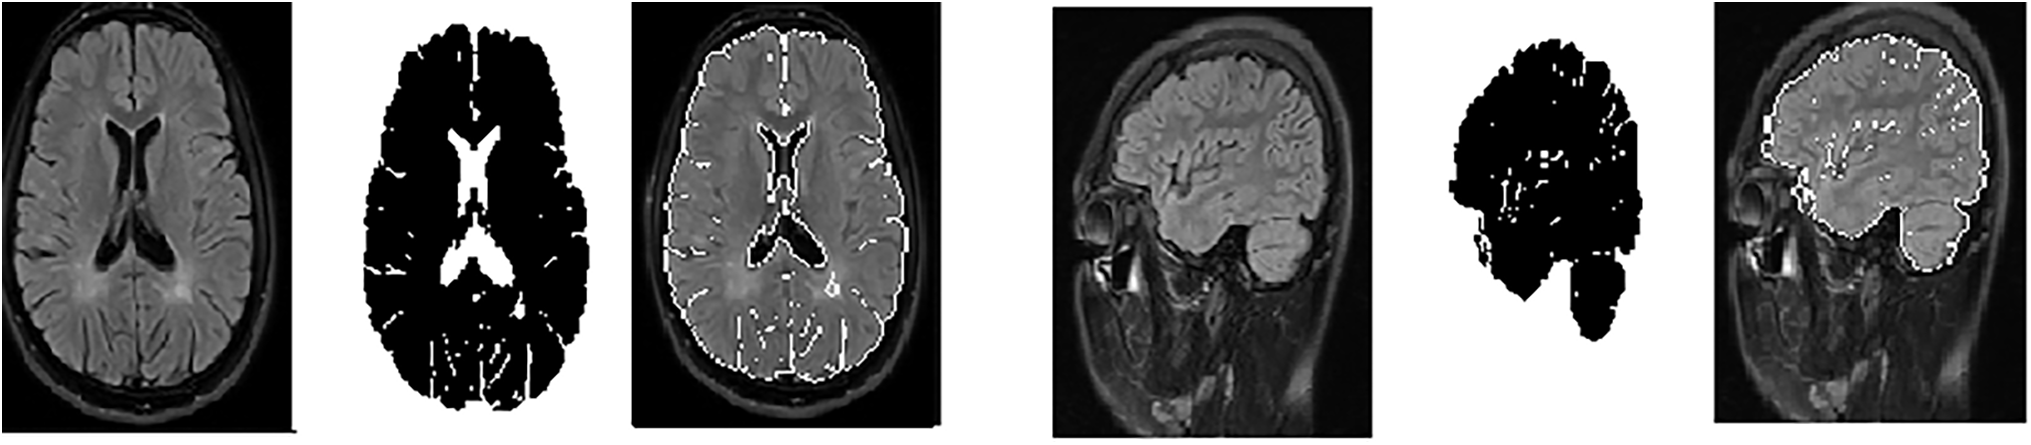

The contour evolves until convergence is reached, indicating that the contour has stabilized around the border of the brain’s white matter lesion area. The final segmented contour defines a mask that isolates the white matter region of the brain [36]. Fig. 3 shows random samples from the axial and sagittal MS dataset after using the GVF algorithm for segmentation.

Figure 3: Samples from the axial and sagittal MS dataset after segmentation and ROI (Region of interest) identification. (a): Original images; (b): Segmented image; (c): Select the region of interest

These parameters were carefully chosen to ensure that the GVF algorithm effectively isolates the hyperintense areas within MS lesions, which are often sufficient for accurate classification by the CNN models used in this study, as Table 2. The goal was to identify the diagnostically relevant parts of the lesions, even if the entire lesion is not segmented, as these hyperintense regions can provide enough information for accurate MS detection.

The intention behind using GVF was to focus on the most hyperintense areas or edges within the MS lesions, which are often sufficient for classification. It is true that in some cases, not the entire lesion is segmented. However, the aim was to identify the most diagnostically relevant parts of the lesions, as even small portions of hyperintense areas can provide enough information for the CNNs to accurately detect MS.

In Fig. 3, the segmented images are used as input to the CNNs. The process of selecting the ROI was as follows: After applying GVF for segmentation, the white matter lesions were isolated from the surrounding brain tissue. This segmented area, containing the lesions, was then designated as the ROI. The ROI is essentially the area of the image where MS-related features are most prominent, ensuring that the CNNs focus on the most relevant parts of the image.